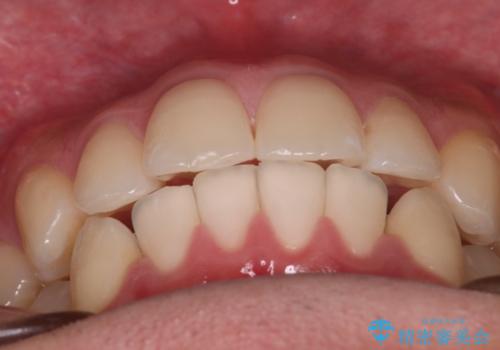

患者様よりシュミレーション通りに歯が動くか心配との事だったので

出来るだけ計画通りに歯を動かすために、マウスピース1枚あたりの使用時間を長めに使っていただきました。

そのため、多少治療期間が延びましたが、リファイメント(マウスピースの再発注)なしで終了することができました。